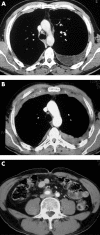

Two case histories are described of pleural and anterior mediastinal fibrosis presenting as a continuous fibrotic process with thick parietal pleural plaques extending from one pleura to the contralateral pleura through the retrosternal area, and with retroperitoneal fibrosis. Follow-up over 4 years in one case demonstrated rapid progression of disease, with pleural fibrosis preceding retrosternal and retroperitoneal fibrosis. Histopathological analysis in both cases showed non-tumoral fibrosis with broad fibrous bundles surrounding fibroblasts (and lymphocytes in one case). Possible causes such as infections and exposure to ergot derivatives were excluded. Both patients had been slightly or moderately exposed to asbestos.